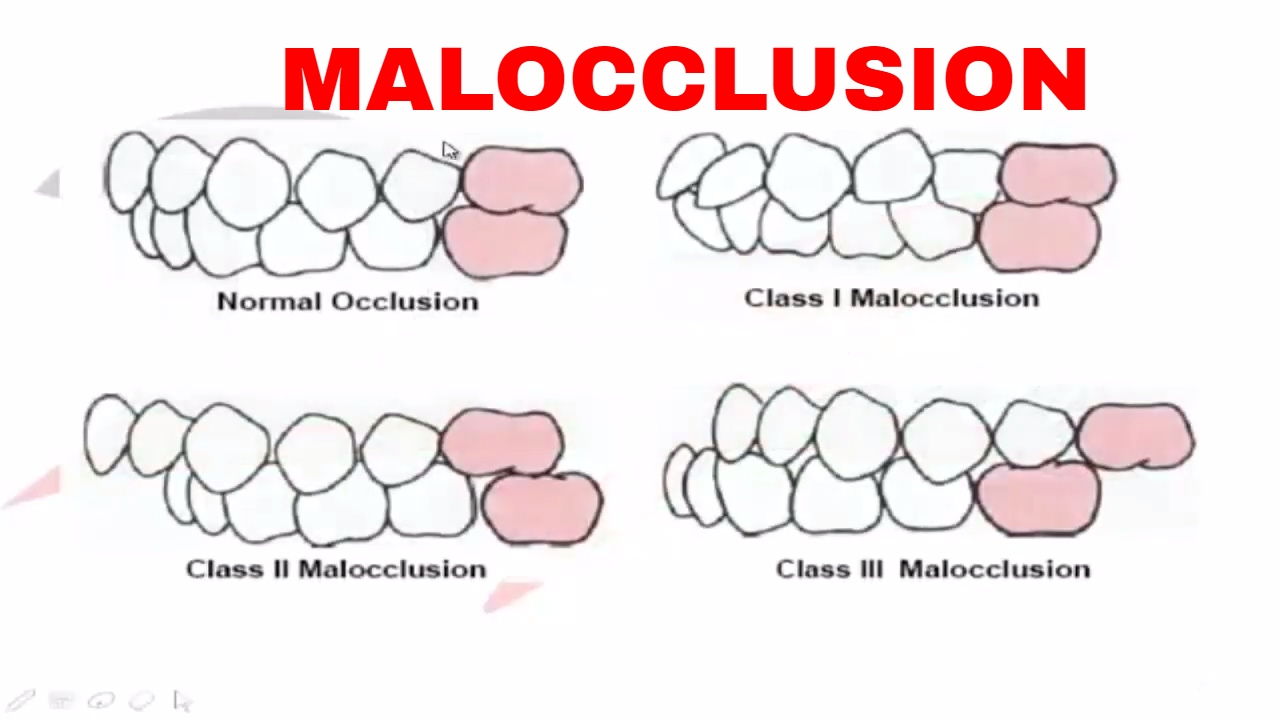

Malocclusion Part I Youtube Class i crowding is when the back teeth are relatively in good occlusion but front teeth are not perfectly straight. Beginning with the corrective orthodontics. this is the first topic crowding and its correction. this video covers all in all crowding. . . . . .

Malocclusion Class I Youtube Class i malocclusion with severe lower anterior crowding and increased overjet treated without extraction. Angle determined that class i malocclusions involve mild crowding and positional or rotational aberrations. class ii malocclusions include the upper incisors creating noticeable “overjet” (tilting outwards) and the upper incisors tilting labially (towards the lips). An overview of the case resulted in the damon ultima psl with variable torques utilized correcting the malocclusion with resolution of the significant crowding and lack of overbite along with substantial arch development. Despite this strong molar connection, patients with class i malocclusion may show additional dental anomalies, such as crowding, spacing, rotations, or misalignment of individual teeth . understanding how and when this malocclusion develops is important to comprehend its etiology.

Class I Crowding Youtube An overview of the case resulted in the damon ultima psl with variable torques utilized correcting the malocclusion with resolution of the significant crowding and lack of overbite along with substantial arch development. Despite this strong molar connection, patients with class i malocclusion may show additional dental anomalies, such as crowding, spacing, rotations, or misalignment of individual teeth . understanding how and when this malocclusion develops is important to comprehend its etiology. Crowding is an increasingly common type of malocclusion caused by a discrepancy in tooth jaw size that leads to twisted and misaligned teeth. two methods to treat this malalignment are tooth material reduction and arch width expansion. Class i malocclusions with severe crowding and tooth size discrepancies may be successfully treated orthodontically with extraction therapy, and co management with other specialists. correction of the discrepancies will optimize occlusal result (overjet, overbite, midline shift, and smile esthetics). Ackerman profitt system of classification involves steps to assess malocclusion. crowding, spacing, cross bite, open bite, deep bite, bimaxillary protrusion, rotations, and other dental problems are discussed, along with their causes and management options. Despite all this, treatment results do not always remain stable. the most common type of malocclusion in mixed dentition patients is crowding. it occurs when there is a discrep ancy between the size of the tooth mass and the size of the supporting bony bases. two treatment strategies used to correct this problem are extraction and expan sion.

Crowding Youtube Crowding is an increasingly common type of malocclusion caused by a discrepancy in tooth jaw size that leads to twisted and misaligned teeth. two methods to treat this malalignment are tooth material reduction and arch width expansion. Class i malocclusions with severe crowding and tooth size discrepancies may be successfully treated orthodontically with extraction therapy, and co management with other specialists. correction of the discrepancies will optimize occlusal result (overjet, overbite, midline shift, and smile esthetics). Ackerman profitt system of classification involves steps to assess malocclusion. crowding, spacing, cross bite, open bite, deep bite, bimaxillary protrusion, rotations, and other dental problems are discussed, along with their causes and management options. Despite all this, treatment results do not always remain stable. the most common type of malocclusion in mixed dentition patients is crowding. it occurs when there is a discrep ancy between the size of the tooth mass and the size of the supporting bony bases. two treatment strategies used to correct this problem are extraction and expan sion.

Class I Malocclusion Youtube Ackerman profitt system of classification involves steps to assess malocclusion. crowding, spacing, cross bite, open bite, deep bite, bimaxillary protrusion, rotations, and other dental problems are discussed, along with their causes and management options. Despite all this, treatment results do not always remain stable. the most common type of malocclusion in mixed dentition patients is crowding. it occurs when there is a discrep ancy between the size of the tooth mass and the size of the supporting bony bases. two treatment strategies used to correct this problem are extraction and expan sion.

Class Iii Malocclusion Youtube